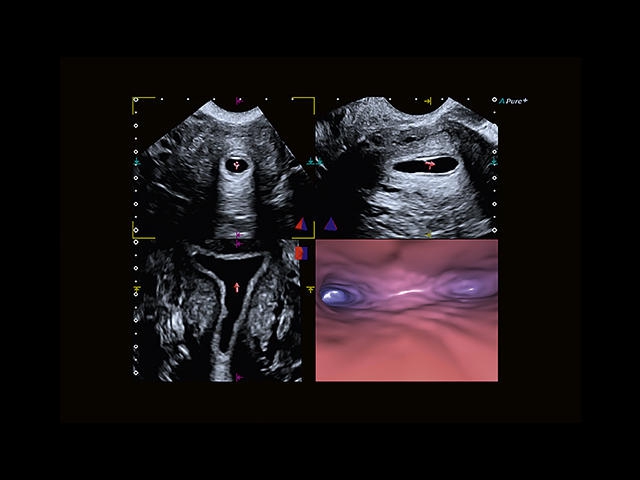

Обновленная версия легендарного УЗ-сканера. Стационарный аппарат экспертного класса Aplio 500 Toshiba NEW, визуализирует анатомические структуры в высоком разрешении. Модель позволяет выявить микрокальцификаты, новообразования, нарушения в работе сердца, сосудов и мышц. Присутствует функция виртуальной эндоскопии, 4D-сканирования, эластометрии тканей, УЗИ с контрастированием. За повышение качества изображения отвечают технологии ApliPure и Superb Microvascular Imaging. Первая задействует возможности пространственного и частотного кодирования, формирует цельный визуальный ряд с сохранением клинических маркеров. Вторая улучшает отображение микрососудистого русла, используя доплеровский эффект. Модель оснащена 21-дюймовым монитором, имеет 4 активных порта. Возможно подключение педиатрических, интраоперационных, лапароскопических и чреспищеводных датчиков.

• MicroPure. Высокотехнологичное решение в области выявления микрокальцификатов – маркеров новообразований злокачественного типа. Маркеры идентифицируются путем изучения затененных изображений целевого участка. Микрокальцификаты отображаются в виде белых пятен.

• SMI. Опция, упрощающая визуализацию микроциркуляторного русла. С ее помощью обследуются сосуды с низкой интенсивностью кровотока, изучаются наиболее тонкие структуры. SMI упрощает диагностику новообразований, минимизирует вероятность ошибки.